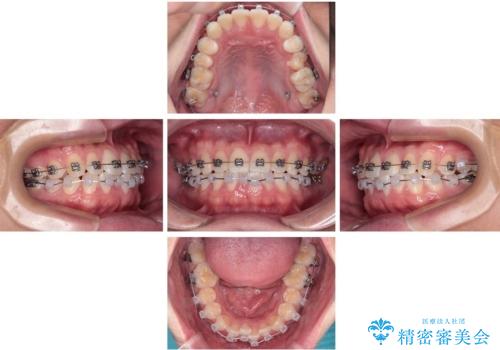

- 矯正装置

- メタルブラケット

・上顎左右の第二大臼歯が頬側へ転移し、シザーズバイト(scissors bite)の状態

・上顎左側第二小臼歯が90度捻転しており、噛み合わせに影響

・費用と期間を抑えるために、多少目立っても効率の良いメタルブラケットを使用

・奥歯のシザーズバイト改善には、口蓋側にアンカースクリュー(TAD)を設置し、矯正用ゴムで内側に牽引

・捻転した第二小臼歯は、ワイヤーと矯正用ゴムの力を用いて正しい位置へ回転移動